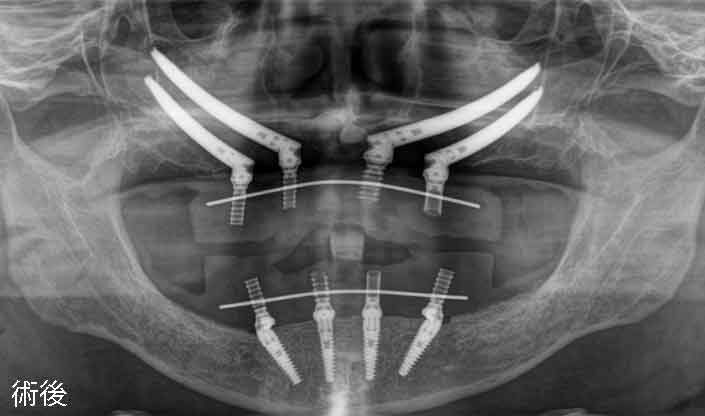

手術日当日 術後

allon4 ザイゴマインプラント

術後ですが静脈鎮静麻酔なので意識が聡明になるのがとても早いです。小休憩後に足取りがしっかりしているのを確認して術後のパノラマX線画像を撮影します。インプラントが適正な位置に施術できているかを確認します。術前が上下、左右ともに噛み合わせのバランスが崩れていましたので、出来るだけ噛み合わせが自然なポジションになるようにインプラントを配置しました。オールオン4インプラントやザイゴマインプラントの全てを45N・m以上の高トルクで締結されています。